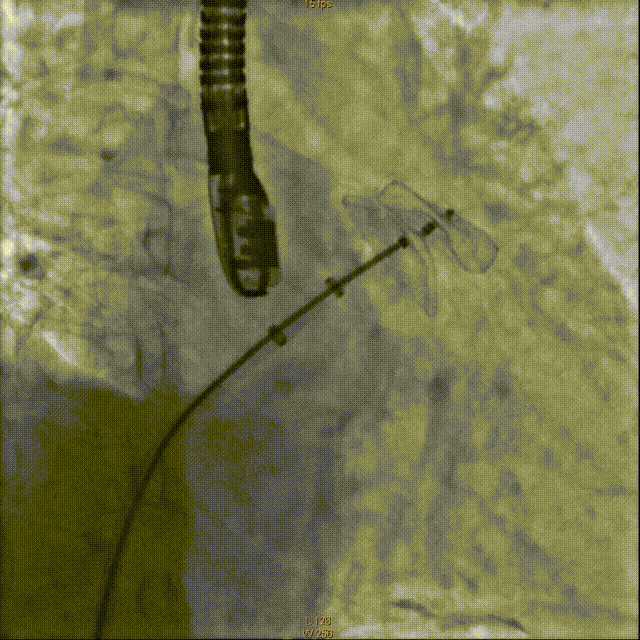

LAA造影

交换右侧8F动脉鞘及加硬钢丝换入1个8F Swartz L1长鞘至上腔静脉口,经Swartz鞘送房间隔穿刺针于PA位及RAO45°及食道超声精确定位房间隔后下位置行穿刺房间隔成功后,交换加硬钢丝至左上腔静脉,置入左心耳封堵器传输外鞘,通过外鞘送入5F猪尾巴导管至左心耳,测量左心房压力24/16mmHg,左心耳压力为25/11mmHg,行左心耳造影,测量左心耳形态及开口经线,左心耳形态为仙人掌状,DSA造影测量20/28mm。

将传输外鞘推送至左心耳开口,结合术前及术中超声检测结果,选择直径26mm左心耳封堵器。严格排气后送入左心耳封堵器,在食道超声及DSARA30°+CAU20°透视下精确定位左心耳封堵器固定盘,造影示位置及封堵良好,透视下释放封堵盘并牵拉,造影及超声检测未见明显漏肩及侧漏,固定盘及封堵盘稳定,贴合左心耳开口好。

释放固定盘并造影